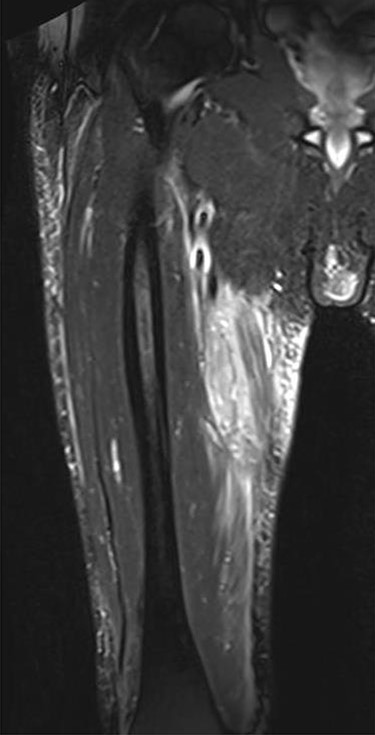

The clinical case consisted of a 79-year-old male patient with a medical history of atrial fibrillation and pulmonary embolism diagnosed 2 years ago. Among the prescribed medications, rivaroxaban was given as an anticoagulant therapy. The patient was lying in bed when a sudden onset of a sprain-like pain appeared on his right thigh region. He had difficulty walking and observed the progression of a large ecchymosis along the thigh, extending from the greater trochanter of the femur to above the patella. Later as the clinical manifestations worsened, the patient arrived at the emergency department. At the hospital, the treating physician noticed edema, ecchymosis and pain confined to the thigh region; therefore, ordered laboratory studies, such as prothrombin time, international normalized ratio and hemoglobin were all within the normal range for the patient’s age and comorbidities. The doctor solicited a magnetic resonance imaging (MRI) study to evaluate the thigh region where a rupture and hematoma regarding the sartorius muscle was evident. The MRI displayed a hyperintense area representing blood collection and discontinuity in the trajectory of the sartorius muscle (Figs 1–3). The hematoma was large in volume, hence surgical drainage was performed. After the procedure, the patient’s pain diminished considerably and was ordered to rest. Posteriorly, the patient began rehabilitation exercises and cooperated with follow-up dates to test progression. The patient attended a follow-up appointment after 6 months of initial presentation where a positive clinical outcome and enhanced walking capacity was observed.

MRI coronal view displaying hematoma and rupture of sartorius muscle.